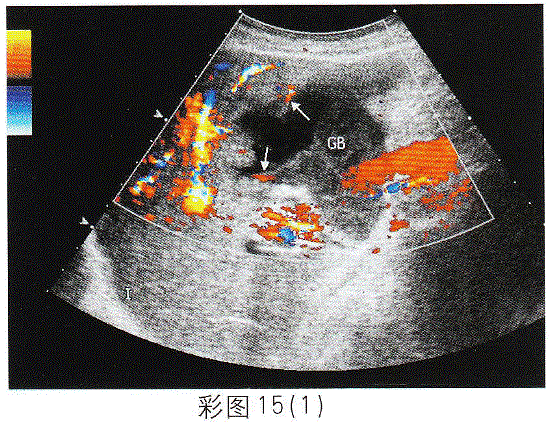

问题 临床资料:男,82岁,自述右上腹疼痛伴高热5天,持续性加重。 临床物理检查:右上腹压痛明显,肌紧张,莫菲氏征阳性。 化验检查:白细胞16.27×10/L,中性粒细胞0.939%。 超声综合描述:胆囊形态失常,内透声不清亮,前壁连续不完整(箭头所示),前壁外可见极低一无回声区,形态不规则,CDFI:囊壁可见动脉血流信号,V28.9cm/s,超声莫菲氏征阳性。见下图及彩图15。 {图3} {图4} {图5} 超声提示:

选项 A.胆囊泥沙样结石(充满型) B.胆囊癌 C.急性胆囊炎胆囊穿孔 D.胆汁淤积

答案 C